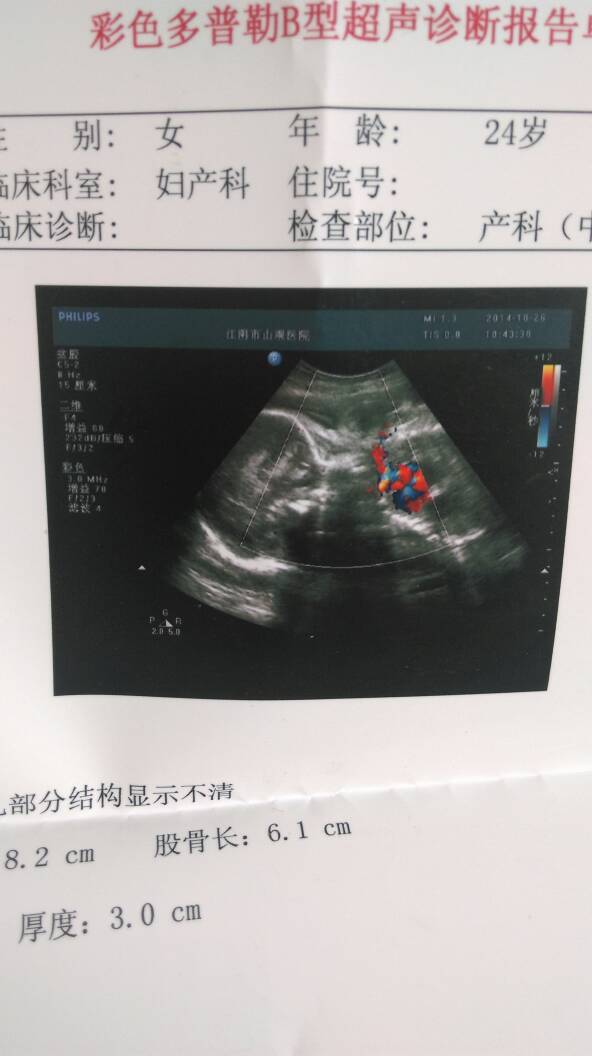

各位有经验的宝妈,有没有能看懂b超单的?帮忙看下宝宝是否健康,是男宝还是女宝啊?

正常,胎位正,没有脐带绕颈,中期妊娠胎盘就已经2级了要定期产检哦